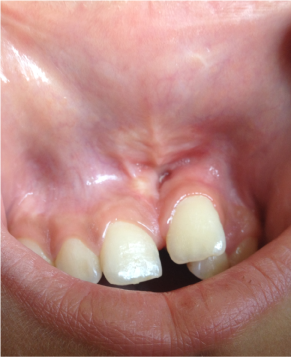

After 6 months Clinical examinations showed no sensitivity to percussion or palpation, and the soft tissues were healthy. Clinical healing and radiographic resolution of the maxillary radiolucency were complete (Figure 5).

Figure 5. Clinical examinations showed the soft tissues were healthy.